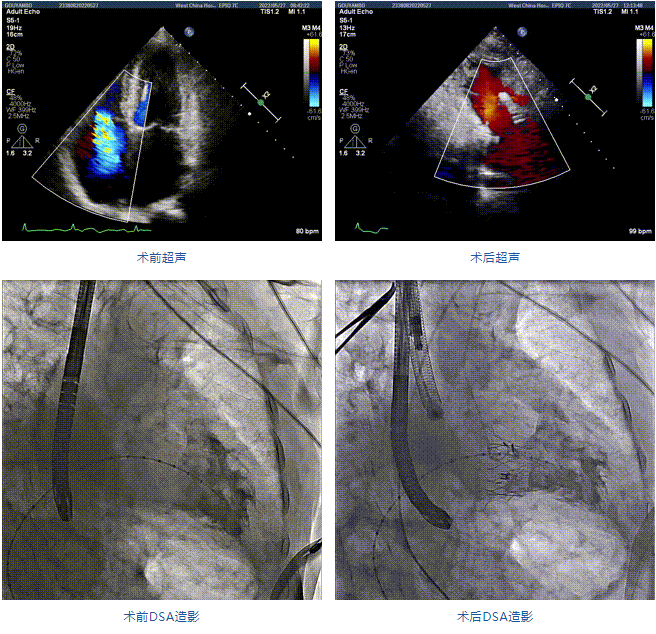

89歲男性。術(shù)前超聲報告顯示:雙房增大,左室壁肥厚,主、肺動脈增寬,三尖瓣重度反流。

團隊前期經(jīng)過多次討論,制定了周密的手術(shù)策略和預(yù)案。由于患者已是近九旬的超高齡老人,傳統(tǒng)外科開胸手術(shù)風險極高,純介入經(jīng)血管三尖瓣替換能夠明顯減少創(chuàng)傷。術(shù)中陳茂及馮沅教授結(jié)合體表定位在造影指示下精準穿刺右側(cè)頸靜脈并預(yù)置兩把血管縫合器。成功建立經(jīng)皮血管入路后在食道超聲和DSA的引導(dǎo)下順利完成人工瓣膜植入,術(shù)后超聲和造影顯示人工三尖瓣同軸性良好,瓣架固定牢靠,無反流和瓣周漏,平均跨瓣壓差降為1mmHg。術(shù)畢收緊預(yù)置的血管縫合器縫線完成止血,縫合效果滿意,在手術(shù)室即刻拔除氣管插管。